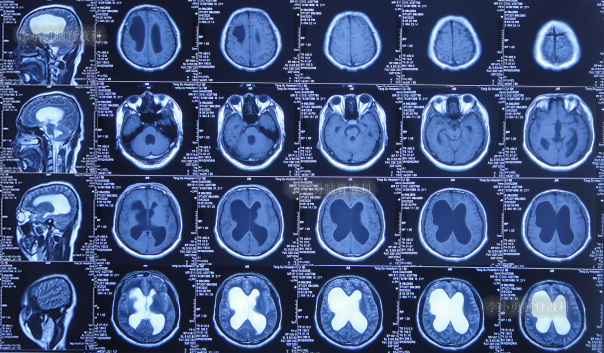

1个月后即2020年5月6日,为治疗脑积水,至陕西省西安市某三甲医院就诊,查头颅核磁示脑积水(图-4)。

图-4:2020年5月6日头颅核磁